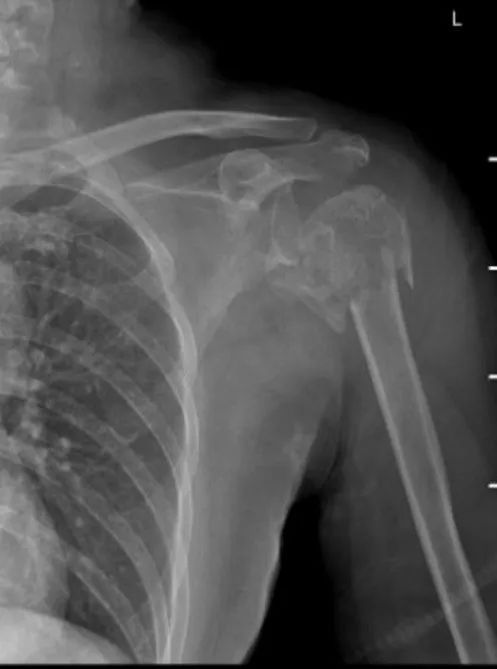

近日,金华籍58岁陈阿姨在兰溪发生车祸,致左肩粉碎性骨折,被送到我院骨伤科住院治疗。

术前三维CT                                                                       术前片

陈阿姨骨折部位损伤严重,骨伤科蒋晶飞主任医师和程江浙医师为患者进行诊断后,考虑简单的切开复位钢板内固定手术难以达到理想效果。综合评估后,为她制定并实施“左肩关节部分置换术”,手术过程顺利。术后,程江浙医师指导并辅助陈阿姨早期功能锻炼。病情稳定后,转到我院康复科继续高质量康复锻炼。经过住院期间的精准治疗和后期的康复健康指导,目前陈阿姨恢复良好。

术后片